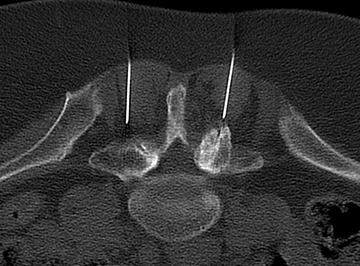

Facetten-Infiltration

Patienten mit Rückenschmerzen z.B. haben oftmals degenerative Veränderungen der kleinen Wirbelgelenke. Hier erlaubt die lokale Applikation von Betäubungsmitteln und ggf. entzündungshemmenden Medikamenten eine Linderung der Beschwerden. Diese sogenannte "Facetten-Infiltration" wird routinemäßig an der gesamten Wirbelsäule (Halswirbelsäule, Brustwirbelsäule und Lendenwirbelsäule) durchgeführt.

Das Beispielbild zeigt die Position der Nadeln zu den kleinen Wirbelgelenken, welche erheblich degenerativ verändert sind. Nach der Prozedur war die Person für fast 6 Monate schmerzfrei.